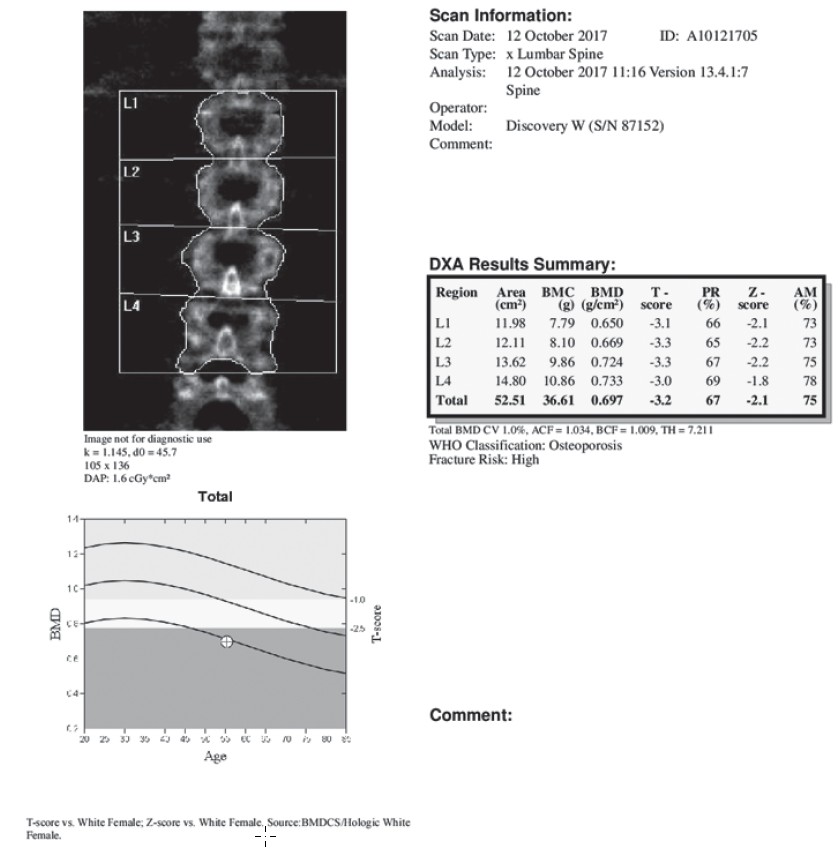

Рис. 7. Остеоденситометрия. Выраженный остеохондроз. Пациентка Б., 65 лет.

Область исследования: поясничный отдел позвоночника, площадь сканируемой поверхности (Area): 52,51 см2, содержание костного минерала (BMC): 3661 г.

Проекционная минеральная плотность костной ткани (BMD): 0,697 г/см2.

Т-критерий = —3,2; Z-критерий = —2,1. Минерализация костей поясничного отдела позвоночника соответствует остеопорозу.